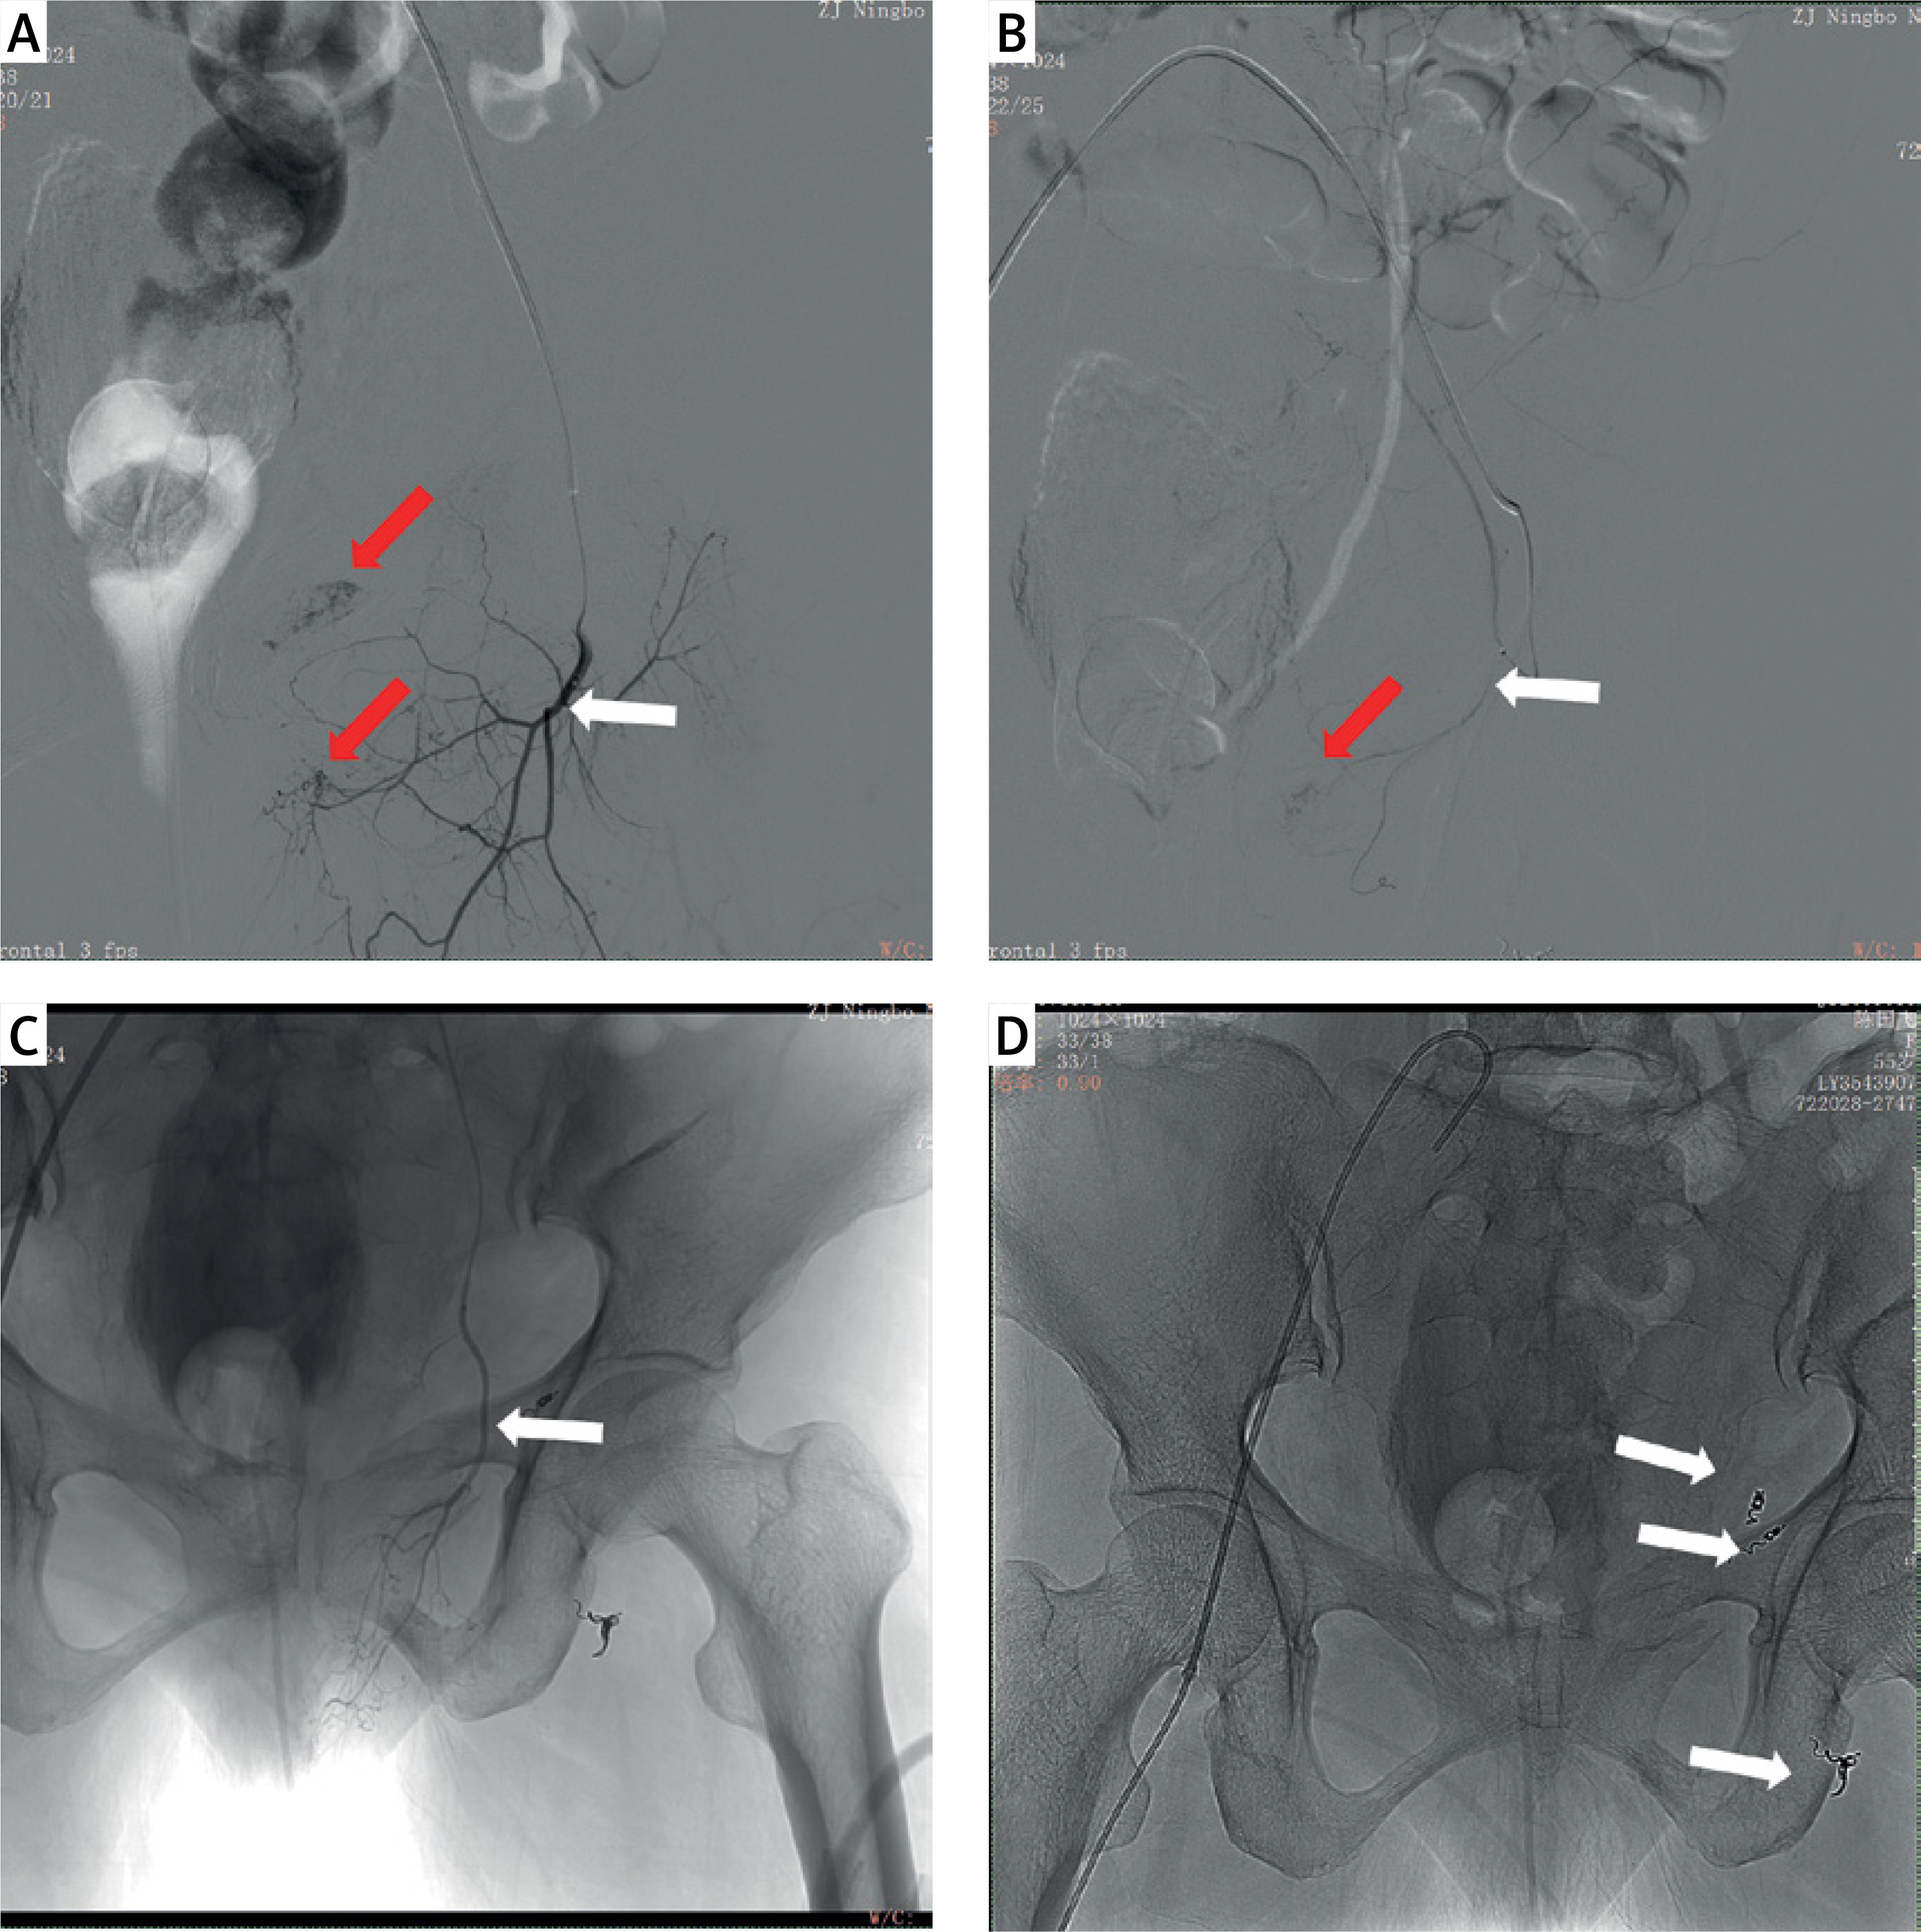

Figure 2

A – Angiography of the left superficial epigastric artery. B – Angiography of the left superficial perineal artery. C – Angiography of the left obturator artery. D – Spring-plug embolisation was performed at the three identified bleeding sites. The red arrows indicate significant bleeding, and the white arrows indicate the embolisation site